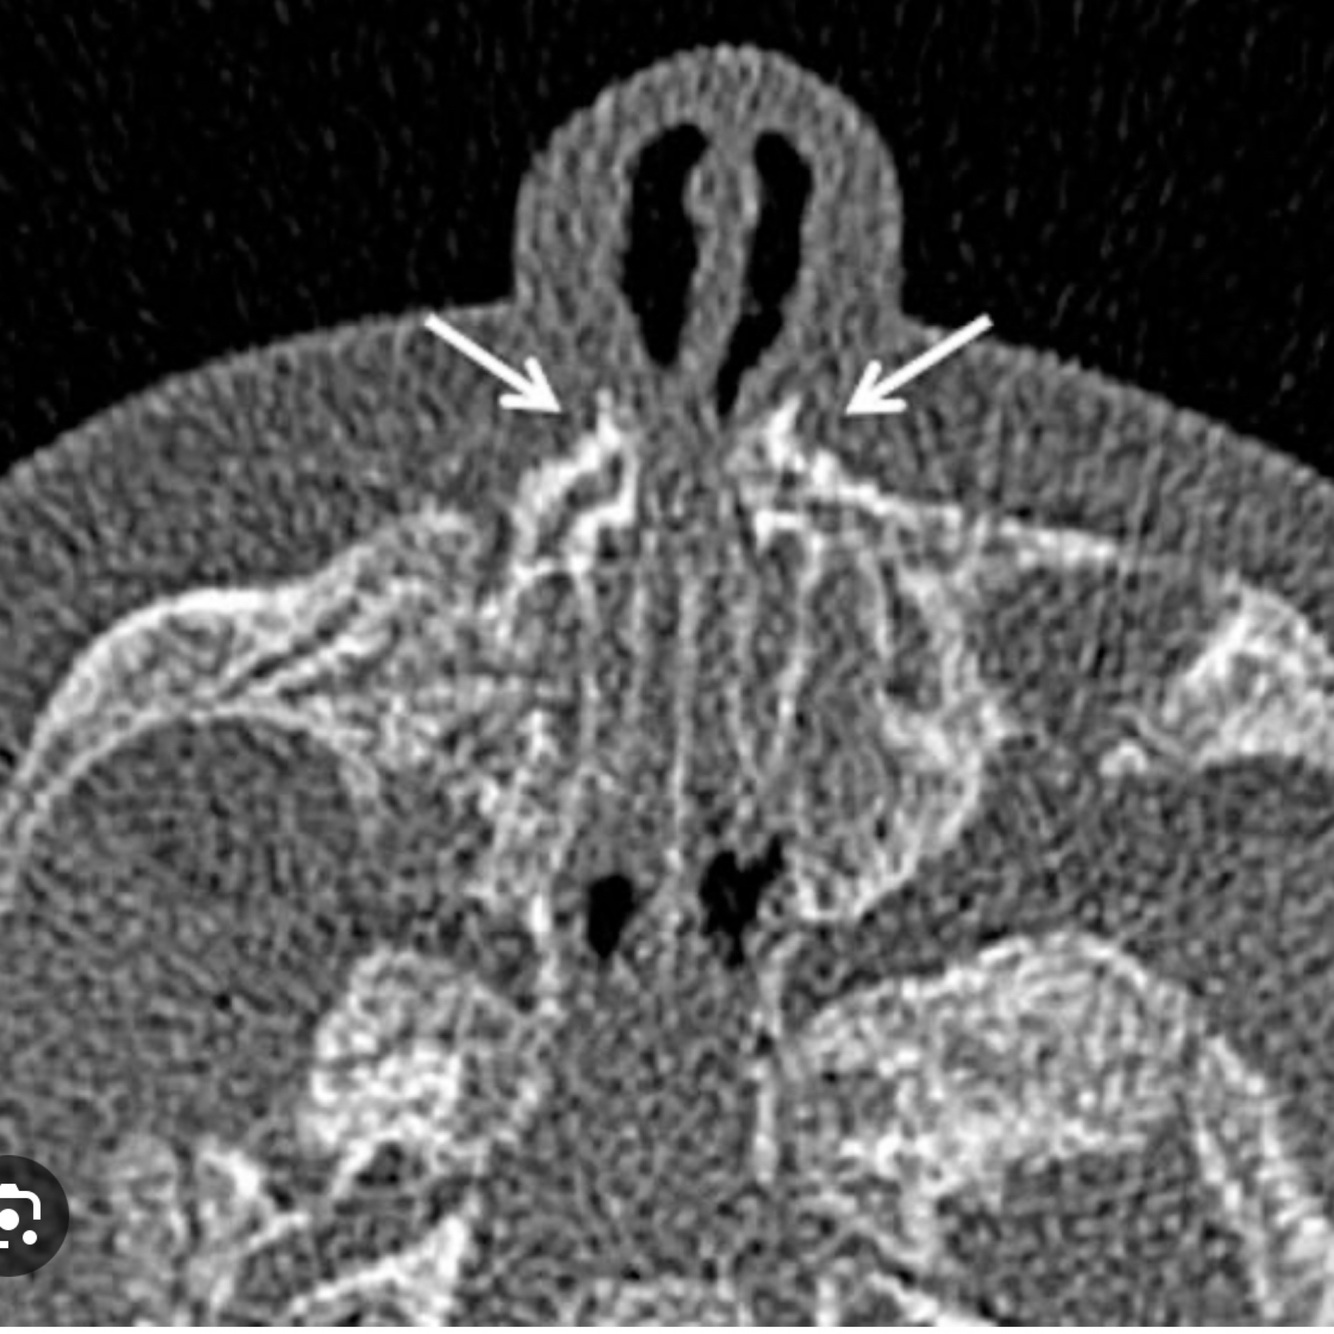

Pyriform aperture stenosis (PAS) is a very rare birth defect where the front opening of the nose is narrow due to an overgrowth in the upper jaw bone (anterior part)

Other is choanal atresia (posterior part)